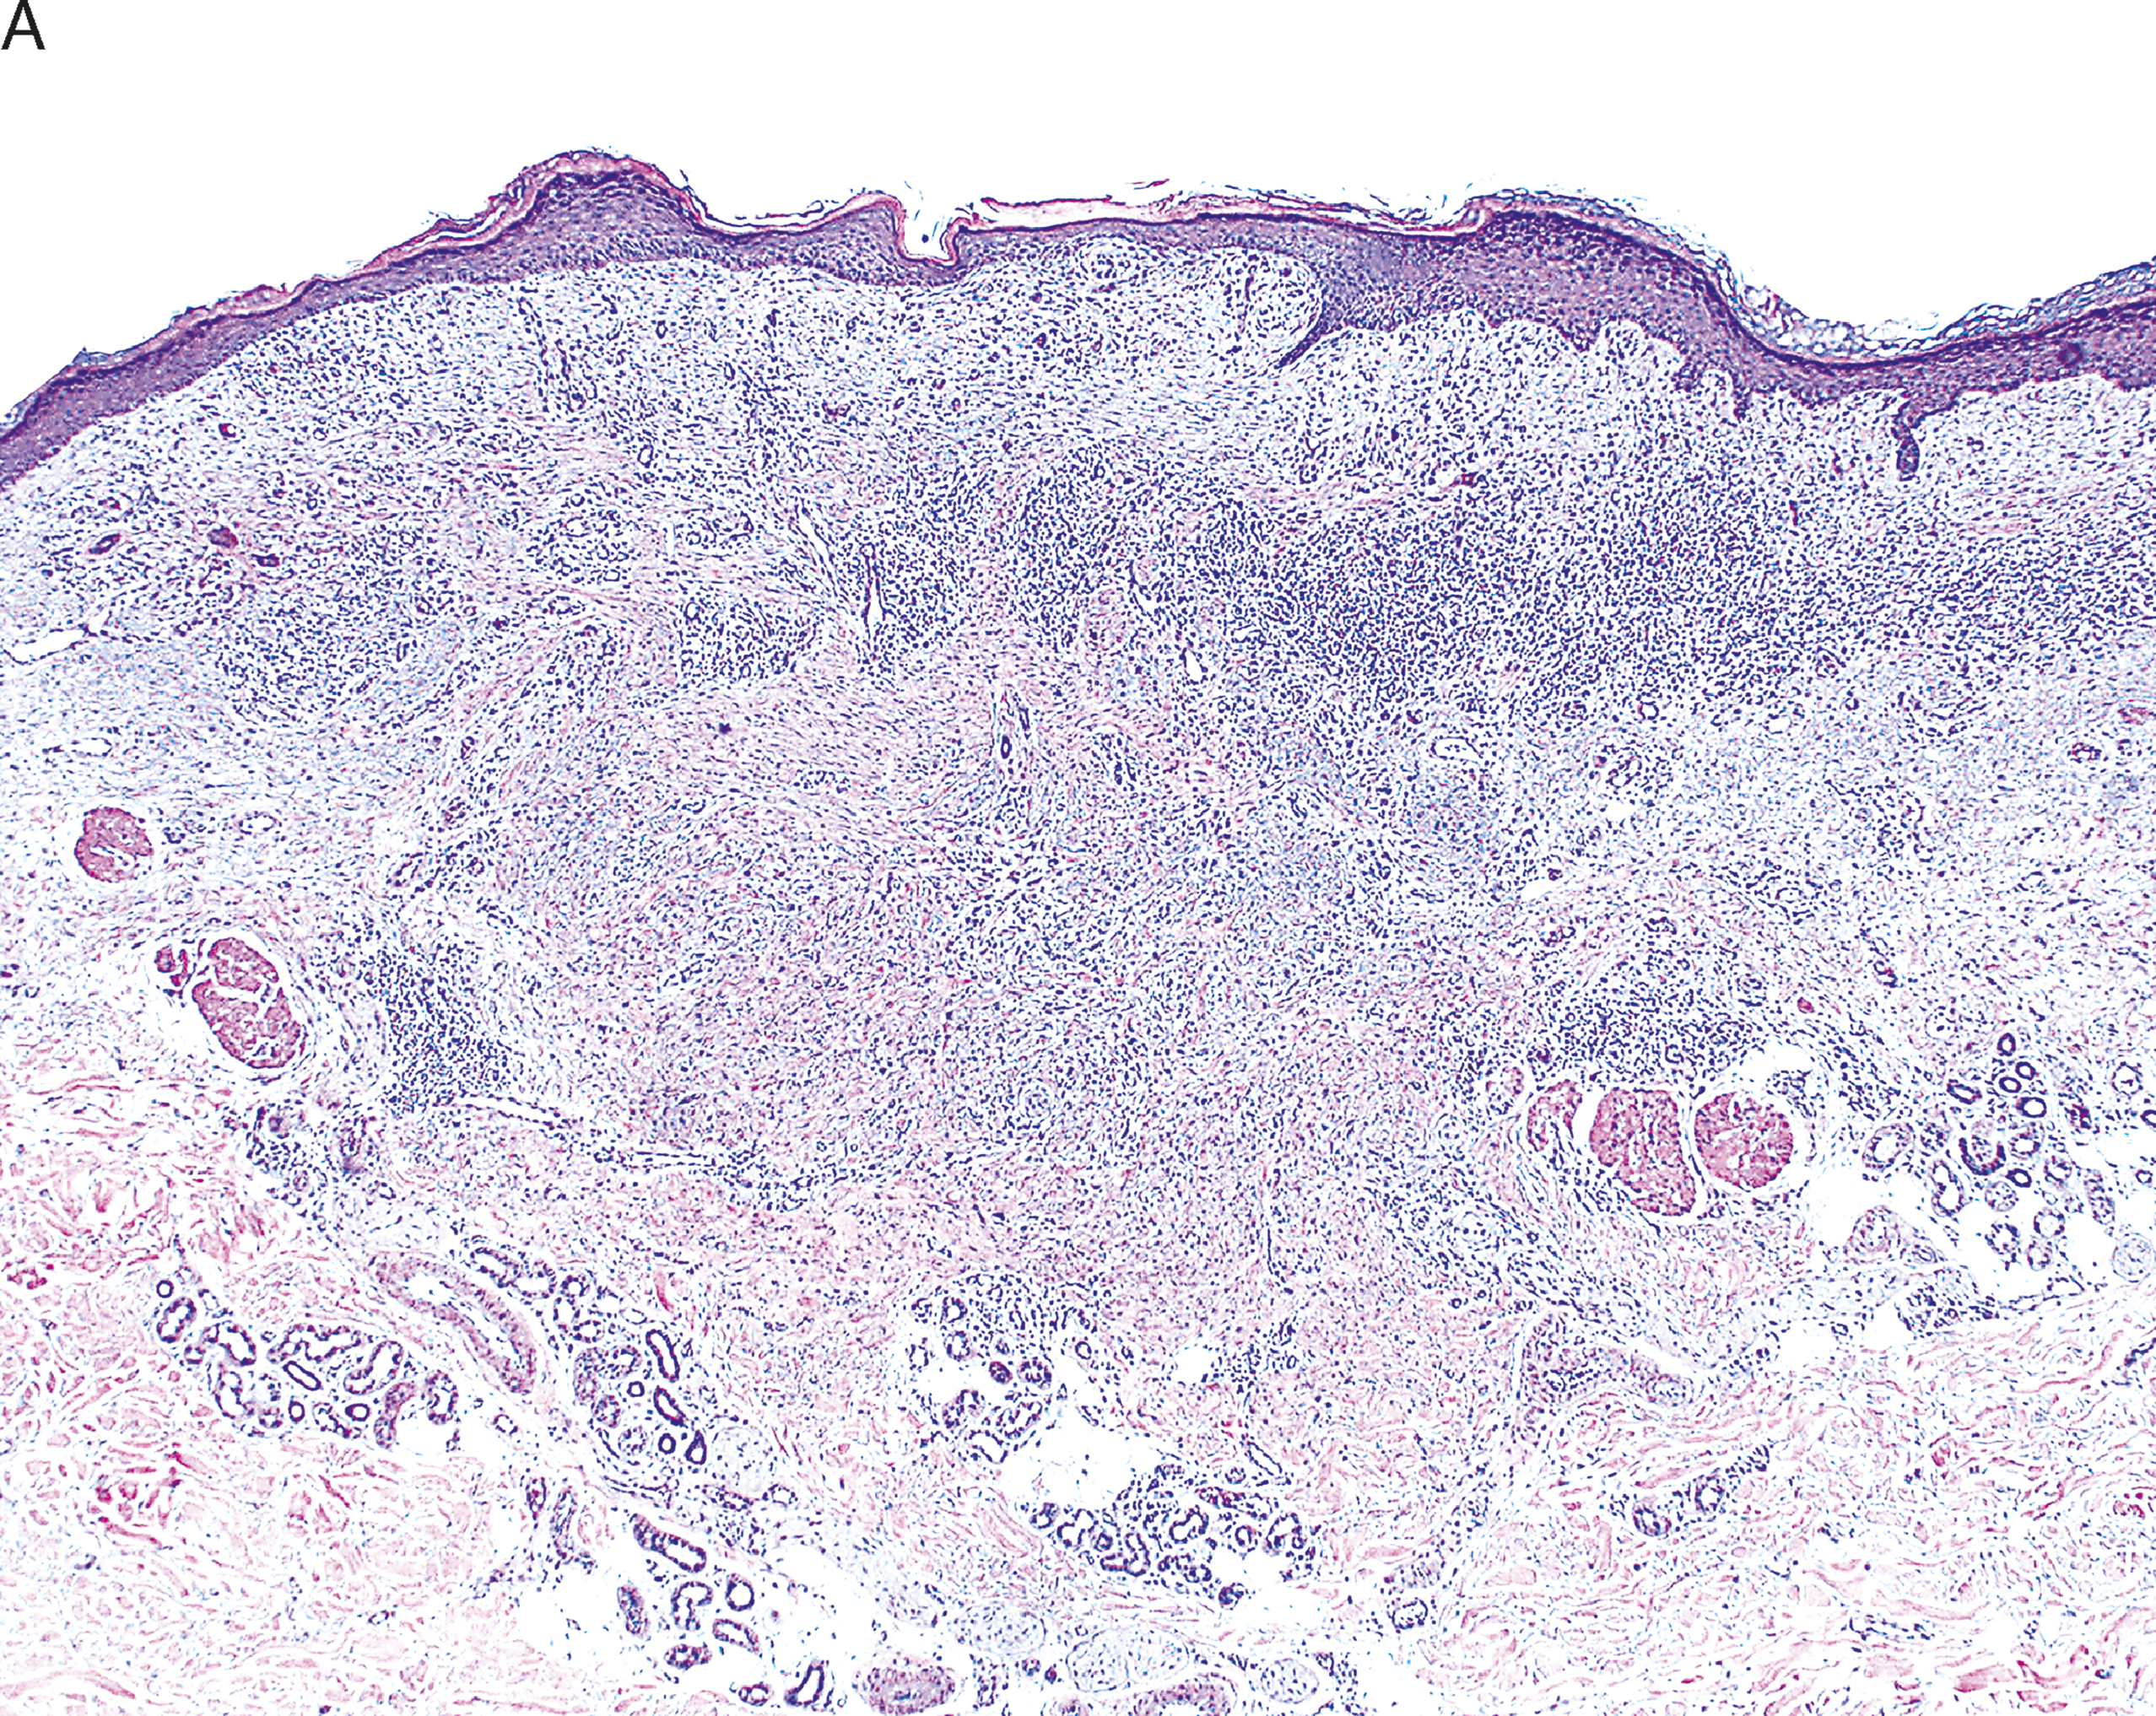

Histopathological photomicrograph of organs/tissues of vehicle control | Download Scientific Diagram

Histopathological photomicrograph of organs/tissues of vehicle control | Download Scientific Diagram

Histopathological photomicrograph of organs/tissues of vehicle control | Download Scientific Diagram,

Histopathological photomicrograph of organs/tissues of vehicle control | Download Scientific Diagram,.jpg) Anatomical pathology - Wikipedia,